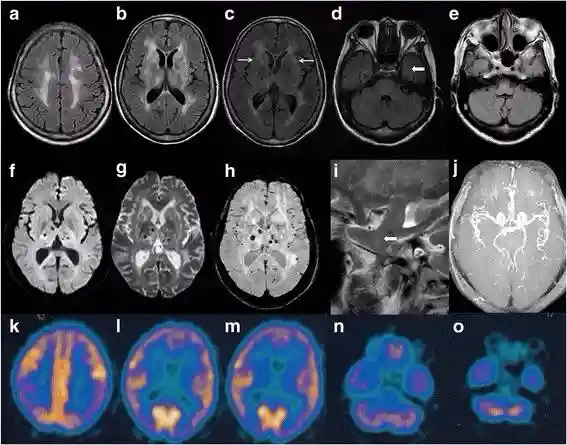

FFI患者的头颅成像